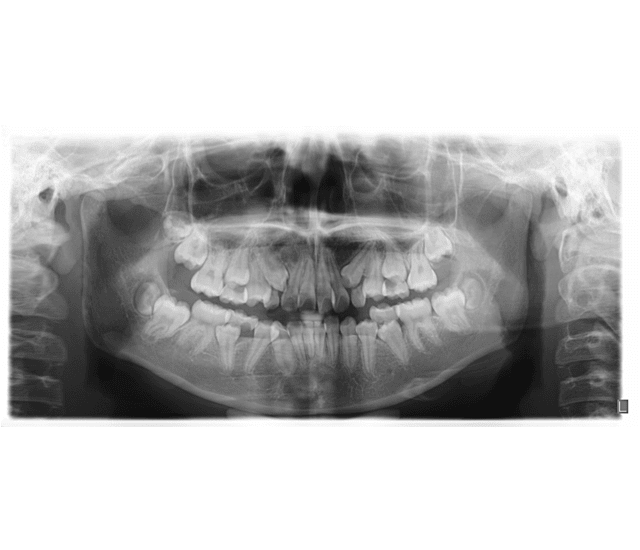

Clove clinics use the latest x-ray technology to diagnose oral health problems in a painless, non-invasive way. Though exposure to radiation can pose health risks, Clove uses sophisticated, portable x-ray equipment that limits this exposure to negligible levels. Clove clinics also use lead aprons and lead thyroid collars to protect doctors and patients from radiation. Finally, Clove clinics adhere to the ALARA (As Low as Reasonably Achievable) principle, as defined by the U.S. Code of Federal Regulations 10 CFR 20.1003. The principle directs medical establishments to identify and use ways to minimize the exposure of medical personnel, patients and clinical staff to radiation.